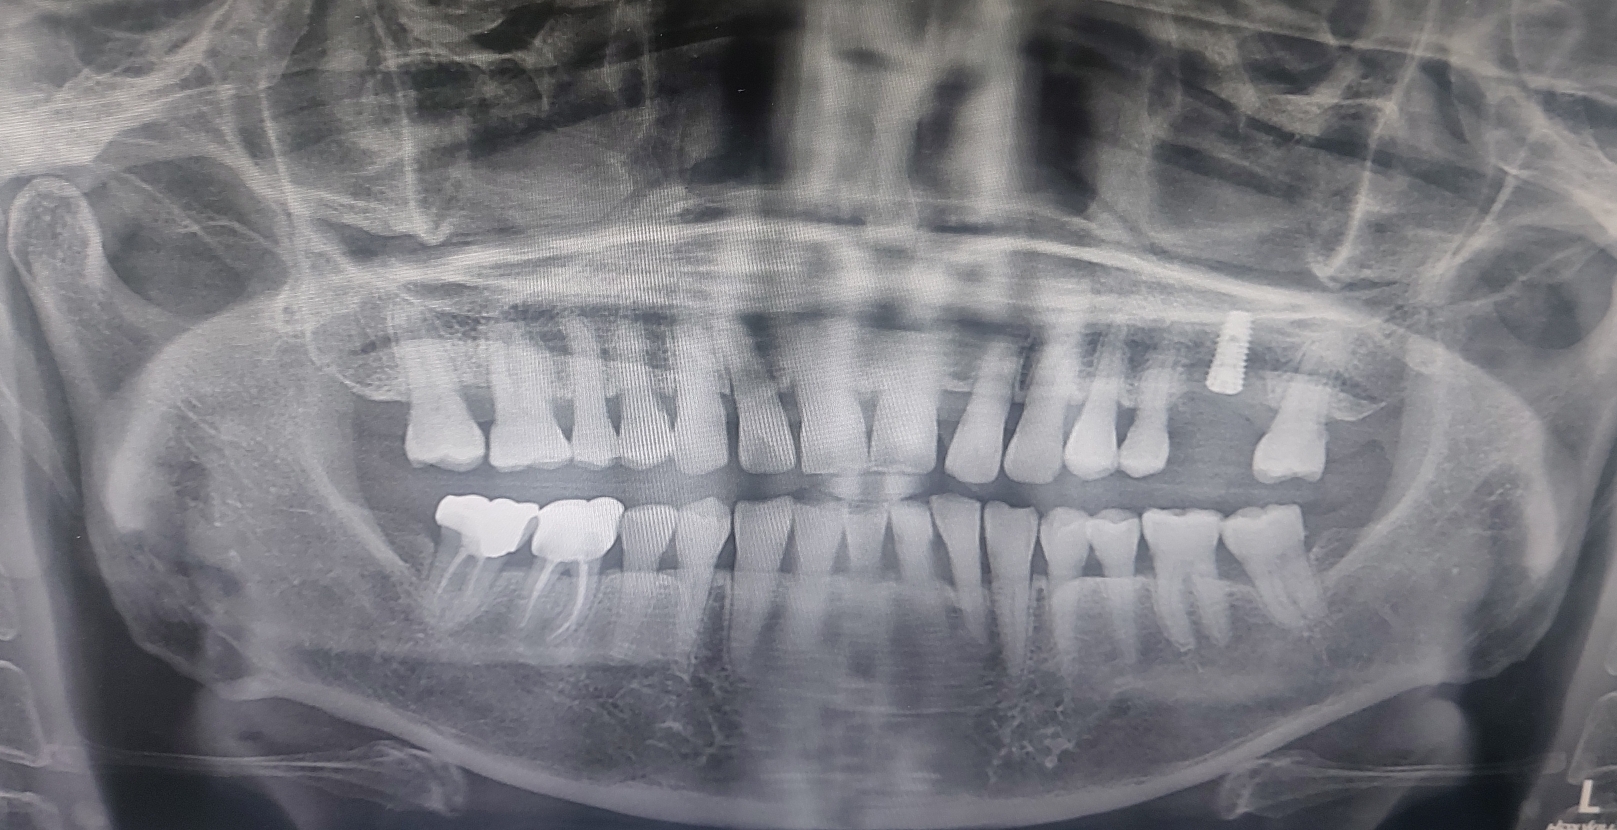

제가 근래에 수술한 보험임플란트 증례들을 보여드리겠습니다.

아래에 3개의 증례는 제가 이번주에 보험으로 수술하신 환자분들의 방사선 사진입니다. 2개정도가 보험이 되기에 꼭 치료가 필요한 부위에 심은 경우입니다.

(2) 아래 환자분은 보험 임플란트를 좌측에 2개를 식립하기 위해서 오셨으나 작은 어금니도 동요가 심하여 발치하고 같이 식립해 드린 증례입니다.